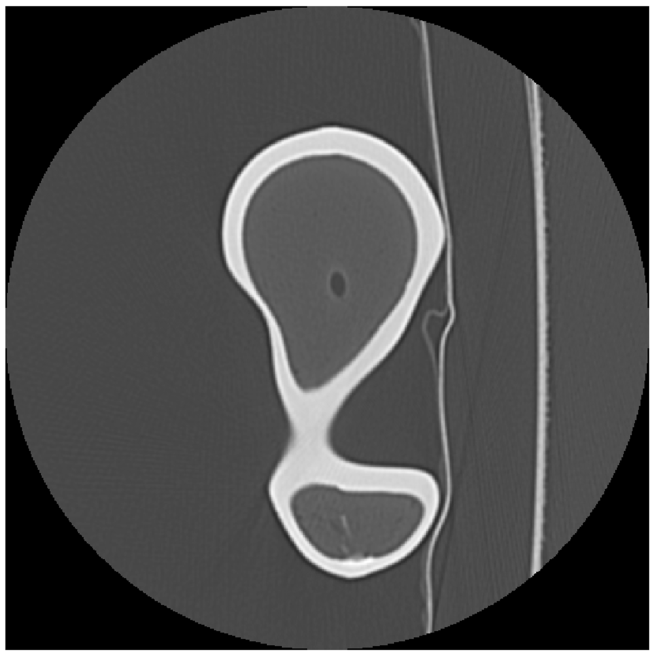

Two outputs may be produced after segmentation refinement (Fig. 2), a high-resolution point cloud model obtained directly from the interpolated image, and a down-scaled version of the high-resolution segmentation. The surface mesh model obtained from the point cloud will be referred as Point Cloud (PC) model. Since image refinement is performed independently in each image, the PC model is produce directly from a set of equally spaced contours by tiling the cloud points. The surface mesh of the down-scaled version was generated in Simpleware ScanIPTM v4.0𝑣4.0v4.0, with standard pre-smoothing and mesh refinement settings [49][50], and will be referred simply as ScanIP Mesh (SM) model. The segmentation pipeline was tested in noise-free and noisy images, corrupted with AWGN with a standard deviation of σNoise=10subscript𝜎𝑁𝑜𝑖𝑠𝑒10\sigma_{Noise}=10 HU. Fig. 5 shows the sub-stpng of the segmentation refinement process when applied to both noise-free and noisy images. The Hausdorff Distance (HD) and the Mean Symmetric Distance (MSD) [51] were applied to evaluate each segmentation outcome.

Figure 5: Segmentation refinement pipeline applied to the Dataset #1: in (a) the original image data without noise; in (b) the image data after de-noising with anisotropic diffusion and image deconvolution; in (c) image cropping and interpolation around the pre-segmented region; and in panel (d) the final segmentation contour superimposed over the pre-segmentation mask; in (e), (f), (g) and (h) image refinement is applied to the same image corrupted with AWGN

Fig. 6 shows the final PC model obtained from the segmentation of Dataset #1 and the comparison with the Nikon Metris LK𝐿𝐾LK V20𝑉20V20 gold standard, whereas Fig. 7 depicts the down-scaled segmentation within Simpleware ScanIPTM v4.0𝑣4.0v4.0 overlapped with reference surface. A close agreement between both PC and SM, and the gold standard is observed for both models. The agreement between the PC and SM model and the gold standard for all noise-free and noisy Datasets regarding the distance measures are summarized in Table II and Table III, respectively.

Figure 7: On left (a) the domain pre-segmentation and final segmentation after refinement for the Dataset #1, in the middle (b) the surface mesh generated with Simpleware ScanIPTM and the reference model, and the comparison between the two models (c)